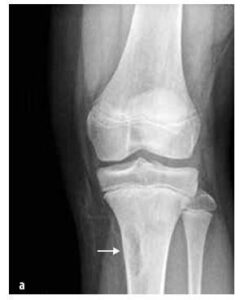

У дитячому віці вони зустрічаються частіше, ніж злоякісні, наприклад, кісткові (остеоїдний остеом, остеобластом, еозинофільний гранульом), сполучнотканинні (фіброзна дисплазія, неосифікуючий фібром (див. малюнок № 7)), кісткові кісти, хрящові (остеохондром, енхондром, хондробластома) та інші (синовіальний гемангіом і пігментний вілонодулярний синовіїт).

Зображення № 7

Неосифікуючий кістковий фібром